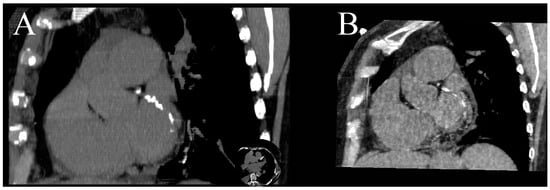

5.3. Radiation Dose Reduction

Coronary CTA originally had one the highest doses of radiation of all CT examinations; thanks to the development of prospective ECG-gating, current modulation and iterative reconstruction algorithms, it has been radically decreased, even to below 1 mSv [10]. It can be further reduced by omitting the noncontrast phase and using DECT’s capabilities of creating virtual unenhanced images (VUIs) [13,24]. Many phantoms and human-based experiments have proved that there is a strong correlation between the Agatston score calculated from the real unenhanced images and VUIs. However, none of the vendors that provide DECT scanners have FDA- or EU-approved Agatston scoring software for use with DECT contrast images [4,10,14,24,47]. In order to use calcium scoring from VUIs in routine clinical practice, precise software has to be modified, because it uses a threshold of 130 HU to extract calcium, whereas water (iodine) maps are coded in element concentrations, making automatic extraction impossible (Figure 5). Most vendors also offer a method of obtaining VUIs coded with Hounsfield units, but this method tends to misclassify small calcification as iodine and extract them as well.

Figure 5.

MPR MIP image of true unenhanced image (A) and water (iodine) map (B) showing calcifications in the LCx. The volume of calculated calcifications was 85 mL and 88 mL, respectively. Similar results, showing high correlation between calcium volume calculated from TUN and VUIs, were reported by [24].